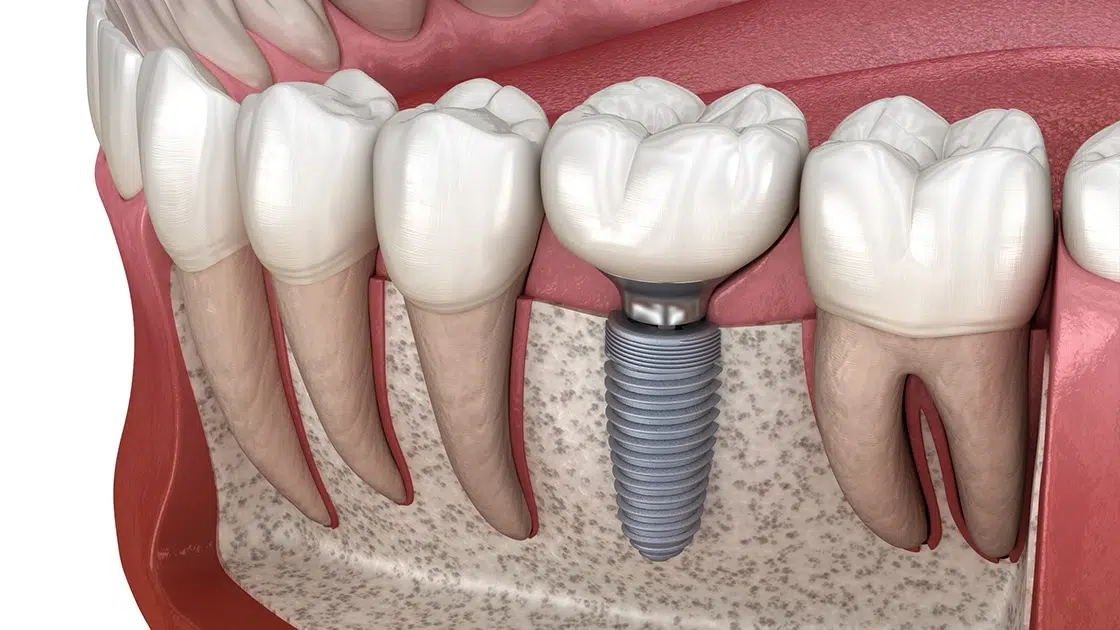

Dental Implants

Complete implant solutions to restore missing teeth with permanent results.